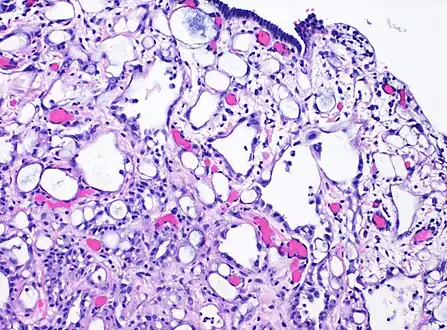

| High-magnification micrograph of an adenomatoid tumor. H&E stain. | |

High magnification of the same case, showing the typical[10] features of tubular spaces of varying size composed of flattened cells resembling endothelium.